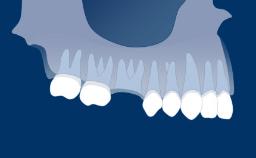

Integration into bone is called osseointegration and this phenomenon essentially revolutionized how missing teeth can be replaced.

Osseointegration has implications for all dentists as well as for patients with any missing teeth. Implants are anchored in bone tissue and penetrate the soft tissue.